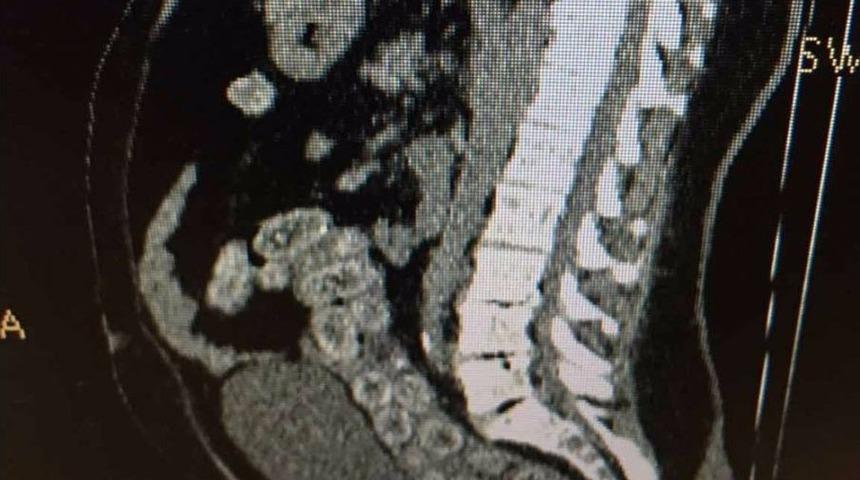

Atatürk Havalimanı’nda, Ganalı uyuşturucu kuryesinin sindirim sisteminden 95 adet kapsül içinde 1 kilo 140 gram kokain çıkarıldı. Sindirim sistemindeki kokain kapsülleri, çekilen MR’da ortaya çıkarıldı.Edinilen bilgiye göre, İstanbul Emniyet Müdürlüğü Narkotik Suçlarla Mücadele Şube Müdürlüğü ekipleri, 23 Kasım’da Belçika’nın başkenti Brüksel’den uyuşturucu madde getirileceği bilgisi üzerine çalışma başlattı. Polis, Atatürk Havalimanı’nda risk analizi yöntemiyle yaptığı çalışmalarda Gana uyruklu R.A.’yı havalimanında gözaltına aldı. Uyuşturucu taşıdığından şüphelenilen R.A.’nin valizinde yapılan aramalarda herhangi bir suç unsuruna rastlanmadı. Şüphelinin uyuşturucu maddeyi yutmuş olabileceğini değerlendiren polis, şüpheliyi hastaneye götürdü. Hastanede sindirim sistemi röntgen filmi ile kontrol edilen Ganalı R.A.’nın midesinde kokain maddesi olduğu değerlendirilen 95 kapsül ortaya çıktı. Uyuşturucu polisi tarafından emniyetteki sorgulanması tamamlanan Ganalı kurye, 26 Kasım Pazar günü adliyeye sevk edildi.Şüpheli R.A., çıkarıldığı mahkemece tutuklanarak cezaevine gönderildi.